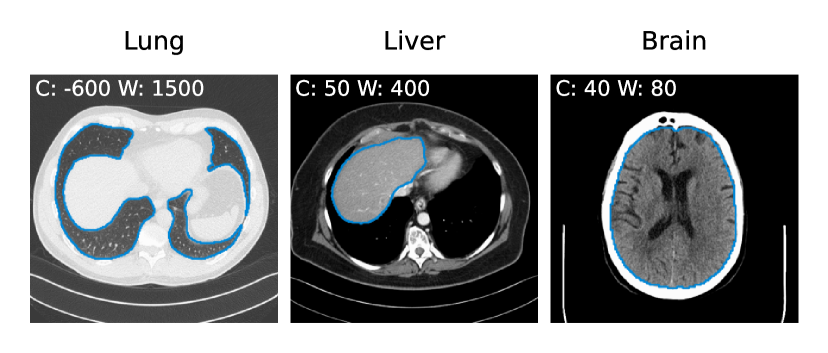

Radiomic features are commonly extracted on segmentations of tumors or entire organs. On the high-dose scans of the test data, we therefore segment the following organs using the TotalSegmentator [63]: lung on chest scans, liver on abdomen scans, and brain on head scans. This segmentation mask is then used for subsequent extraction of 91 radiomic features222This includes features from the following classes (# of features): first order statistics (18), gray level co-occurrence matrix (24), gray level run length matrix (16), gray level size zone matrix (16), neighbouring gray tone difference matrix (4), and gray level dependence matrix (13). using PyRadiomics [64].

Refer to caption

Figure 4: Contour plots of automatic segmentations for three high-dose scans of the test set of lung, liver, and brain. Radiomic features were extracted within these segmentations for low- and high-dose as well as all denoised volumes.

In Fig. 4 we show contour plots of the automatic segmentations of the brain, lung, and liver for three high-dose scans of the test set. We visually verify that segmentations are reasonably good for all 15 scans in the test set. Those segmentation masks are then used to extract radiomic features for all low- and high-dose, as well as all denoised volumes of the test set. Using the same segmentation mask for subsequent radiomic feature extraction of all algorithms ensures a fair comparison, despite possible small errors produced by the automatic segmentation pipeline.